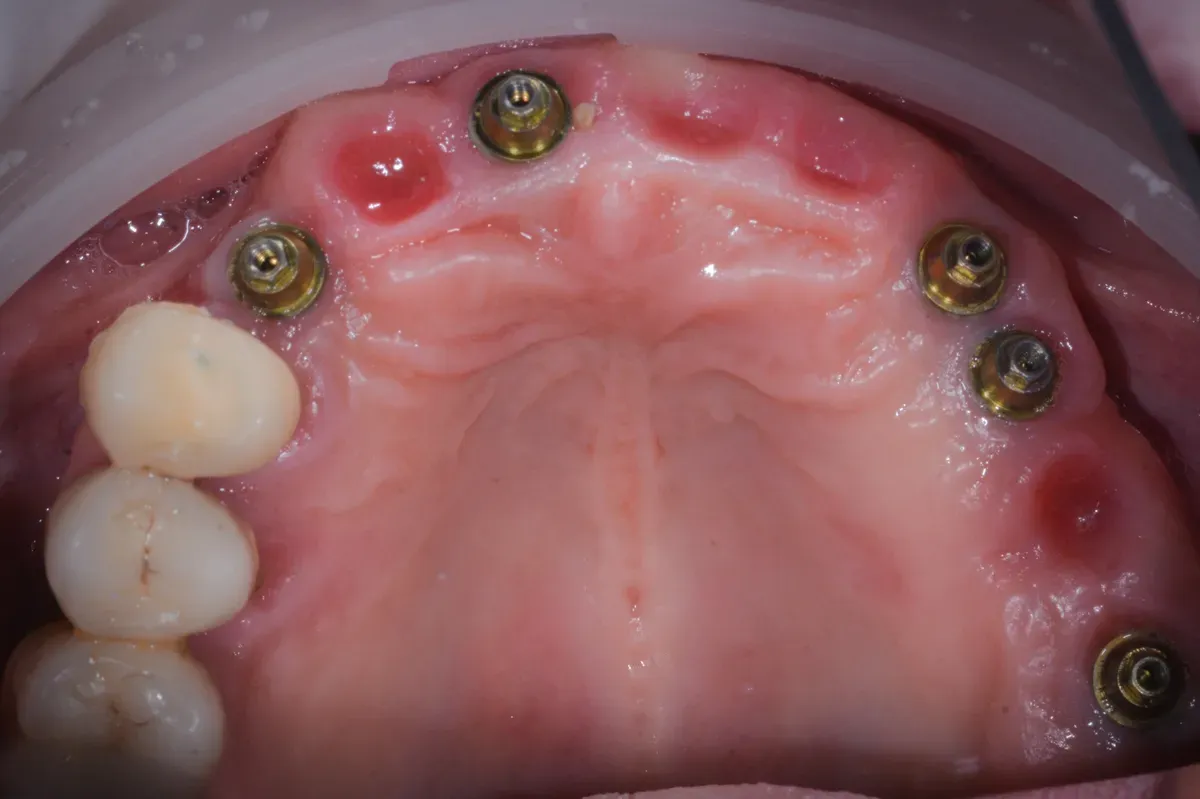

Nelle due figure sottostanti è evidente come la terapia, qui ancora in fase di estrazione dei denti non mantenibili, ottenga il ripristino totale (la rigenerazione) del tessuto alveolare e quindi una forma del tutto simile a quella naturale. E questo si ottiene solo con l’espansione mucosa del sito e senza xenoinnesti di connettivo. Inoltre, nei siti (alveoli) estrattivi non è stato inserito nulla per mantenere la forma: il mantenimento si ottiene solo con la forma del provvisorio che si inserisce per 4 mm all’interno con i “ponti ovoidi”.

Insomma la rigenerazione si ottiene con l’aria, anzi con il sangue che riempe i vuoti e poi grazie alle cellule che colonizzano i sito dai bordi e senza aggiunta di altri materiali. Bello no?

Come si ottiene la rigenerazione mucosa senza xenoinnesti di connettivo? Mediante la tecnica dei ponti ovoidi in un provvisorio inserito 4mm negli alveoli estrattivi, la mucosa si espande naturalmente. Il sangue riempie i vuoti iniziali e le cellule colonizzano il sito dai bordi senza aggiunta di materiali. È una rigenerazione biologica pura.